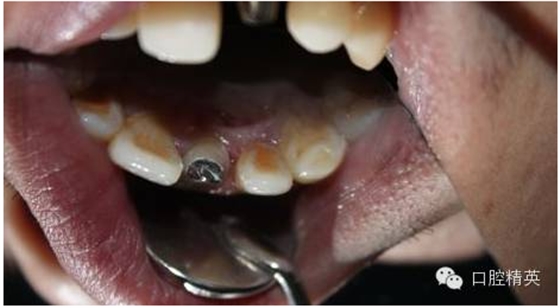

4:舌面觀,

5:頜面觀,排齦,待黏冠